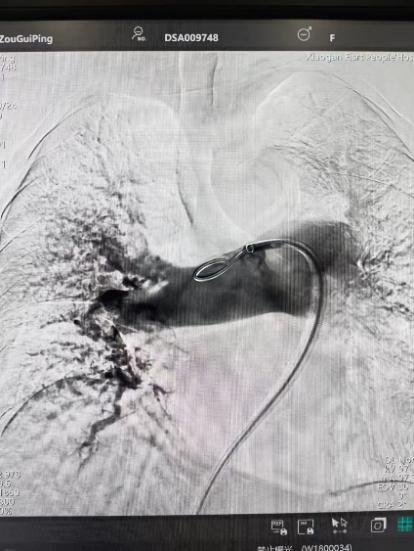

術前

手術在局部麻醉下進行,團隊通過股靜脈穿刺,將專用抽栓導管精準送達肺動脈栓塞部位,利用負壓抽吸技術成功清除大量血栓;隨后,在血栓局部精準灌注溶栓藥物,進一步溶解殘余血栓,恢復肺部血流灌注;同時,為防止下肢深靜脈血栓再次脫落引發(fā)肺栓塞,團隊為患者置入下腔靜脈濾器,整個手術歷時約1小時。術后,鄒婆婆呼吸困難癥狀即刻得到緩解,血氧飽和度顯著提升,右心負荷明顯減輕,目前身體狀況正在逐步恢復中。